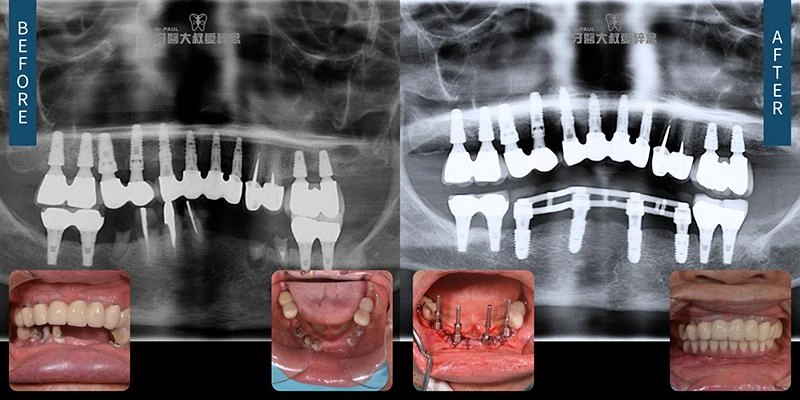

All-on-X, 一日長城